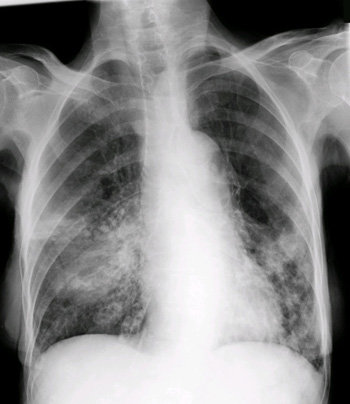

Rx tórax: condensaciones con patrón alveolar en lóbulo inferior izquierdo y en lóbulos medio e inferior derechos. ( Imagen 1)

En nuestro caso clínico una exploración física básica con una auscultación pulmonar alterada, en el domicilio nos indicó la necesidad de pruebas complementarias que incluyeran la Rx tórax (Imagen 1).

La radiografía de tórax (Rx tórax) sigue siendo la prueba “gold standard” para el diagnóstico de la neumonía. Es recomendable realizarla ante la sospecha clínica ya que permite confirmar el diagnóstico, detectar otras enfermedades ó complicaciones y ayuda en la valoración del pronóstico.